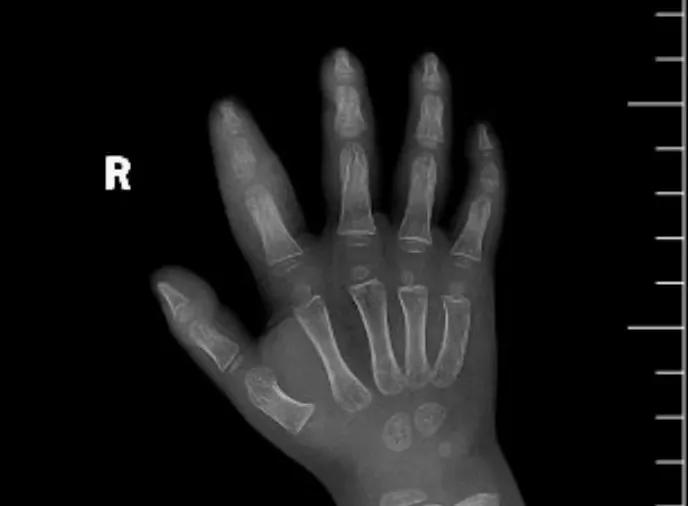

近日,市二院顯微外科接診一名3歲半的小患者,被玉米葉割傷右食指,因家長疏忽大意,導致一個小小的傷口竟然發(fā)展成了骨髓炎。來院時患兒右食指腫脹明顯,既不能伸也不能彎,皮膚發(fā)燙,疼得哇哇大哭。

第三天開始,月月哭鬧不止,一直說手疼,怎么哄也不行,于是在當?shù)蒯t(yī)院治療了10來天,然而月月的手指依然腫得像個胡蘿卜,疼痛感依然存在。此時,月月的媽媽才覺得事情不大對勁,于是經(jīng)過打聽,慕名來到市二院顯微外科。入院后,經(jīng)檢查發(fā)現(xiàn),月月的右食指骨質(zhì)有侵蝕,骨骺有缺損,甚至會影響以后手指的發(fā)育。聽到這個消息,月月媽媽感覺心都揪住了。

隨后,經(jīng)顯微外科團隊充分的討論,制定了科學細致的治療方案,為月月做了感染灶清除及手指的開放引流,并留取了標本做細菌培養(yǎng),為進一步的合理用藥提供依據(jù)。經(jīng)過兩周的治療,月月的手指終于順利消腫愈合,并且手指功能活動良好。說起這一個多月的煎熬,月月媽媽不禁落淚,但總算是治愈了,笑容又重新回到她們一家的臉上。